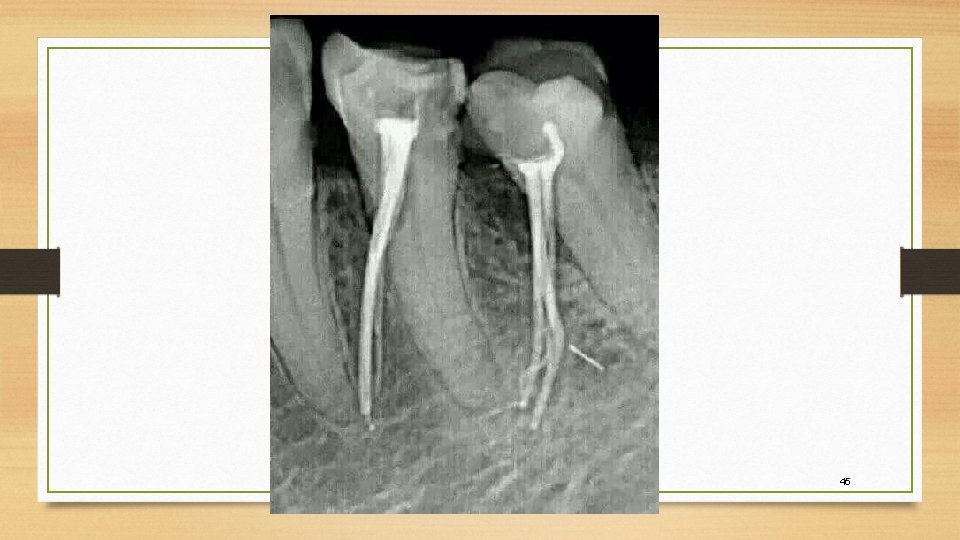

Endodontic Therapy in a 3Rooted Mandibular First Molar Importance of Chapter 54 Endodontics Quizlet study endodontics chapter 54 flashcards from rebecca hannigan's class online, or in brainscape's iphone or android app. study with quizlet and memorize flashcards containing terms like what are periradicular tissues?, what specialists performs root. What is endodontic treatment often referred to as? ( multiple choice) which statement is incorrect concerning the specialty of endodontics? terms in this. Chapter 54 Endodontics Quizlet.